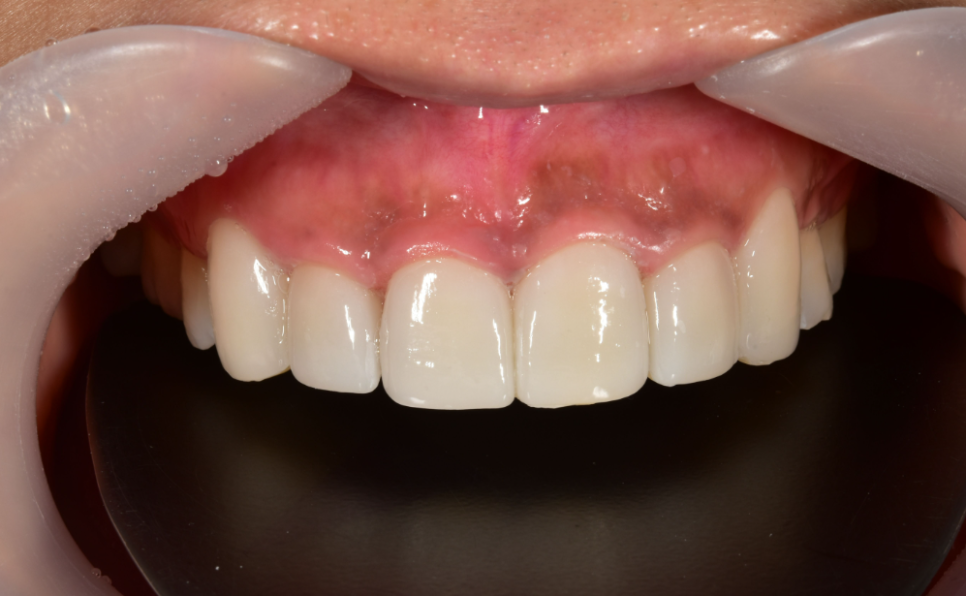

BEFORE

AFTER

이렇게 앞니깨짐과 같이 문제가 생길 경우에는 더욱 자연스럽고 퀄리티 높은 시술을 통해 심미성에서 유리할 수 있도록 실력있는 곳에서 치료를 받는 것이 중요한데요.

특히 하루에 다양한 사람들을 만나는 서비스직에 종사하시는 분들께서는 이러한 부분에 대해 더욱 중요하게 생각하시기 때문에 저희 2D치과를 많은 분들이 찾아주고 계신 것 같아요.

2016년부터 2D치과 대표원장님께서 앞니장인이라는 타이틀이 괜히 생긴 것이 아닙니다. 저희는 앞니 고민으로 내원해주신 많은 환자분들을 치료해드리면서 엄청난 케이스와 임상을 보유하고 있습니다.